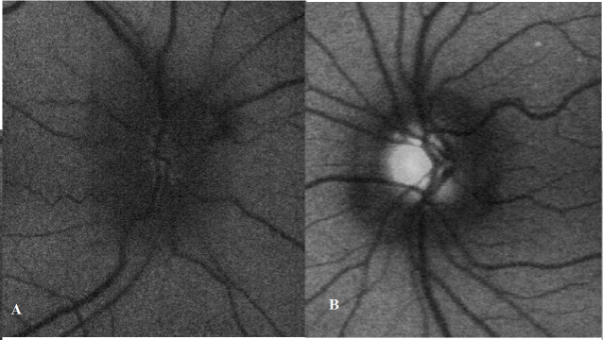

Fundus Autofluorescence

The role of fundus autofluorescence is mainly in diagnosing ODD in a rapid and non-invasive manner. The sensitivity of this test in picking up ODD is around 88% but has the highest specificity.[12] In papilledema, there is hypofluorescence of the disc that extends beyond the margins due to presence of fluid.